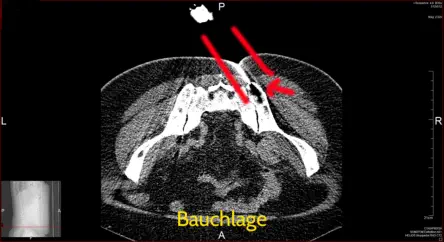

CT - Bilder der Punktion des Beckenkamm

Punktion

Punktion unter CT